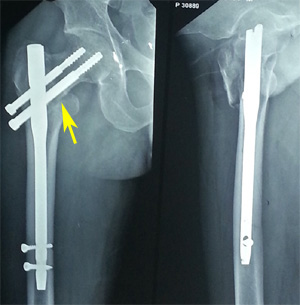

Case 3

A 40-year old male was injured in a road side accident resulting in intertrochanteric fracture of the left femur (AO/OTA 31-A3.1). The patient was submitted to osteosynthesis with PFN. Immediate post-operative radiograph of the patient revealed acceptable NSA, acceptable position and size of screws, restoration of alignment, but not maintaining anterior bony contact. At 3 months post-operative, the patient presented with lateral migration of the lag screw, with the derotation screw maintaining its original position (Z-effect). Patient was kept on strict follow-up, so that any chance of failure of fixation can be detected. At 7 months, patient showed clinico-radiological signs of union. Although, the lag screw moved laterally, but it was still well positioned with regard to the tip apex distance and the fracture was adequately aligned, hence no failure in osteosynthesis occurred. Radiographic images of the patient are presented in Figure 8.

Figure 8b Immediate post-operative radiograph showing restoration of NSA & medial buttress. Also note the acceptable position & size of screws. Arrow in lateral projection showing lack of anterior bony contact.

Figure 8c Three months post-operative radiograph showing lateral migration of the lag screw, with the derotation screw maintaining its original position (Z-effect).